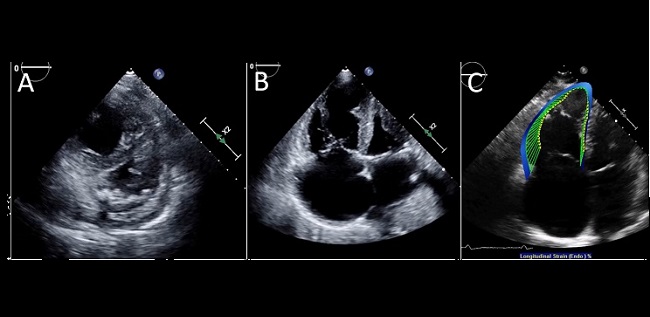

Top Stories in Cardiology: June 2020This month, Julia Grapsa and Mary Norine Walsh describe the many ways COVID-19 affects the heart. |